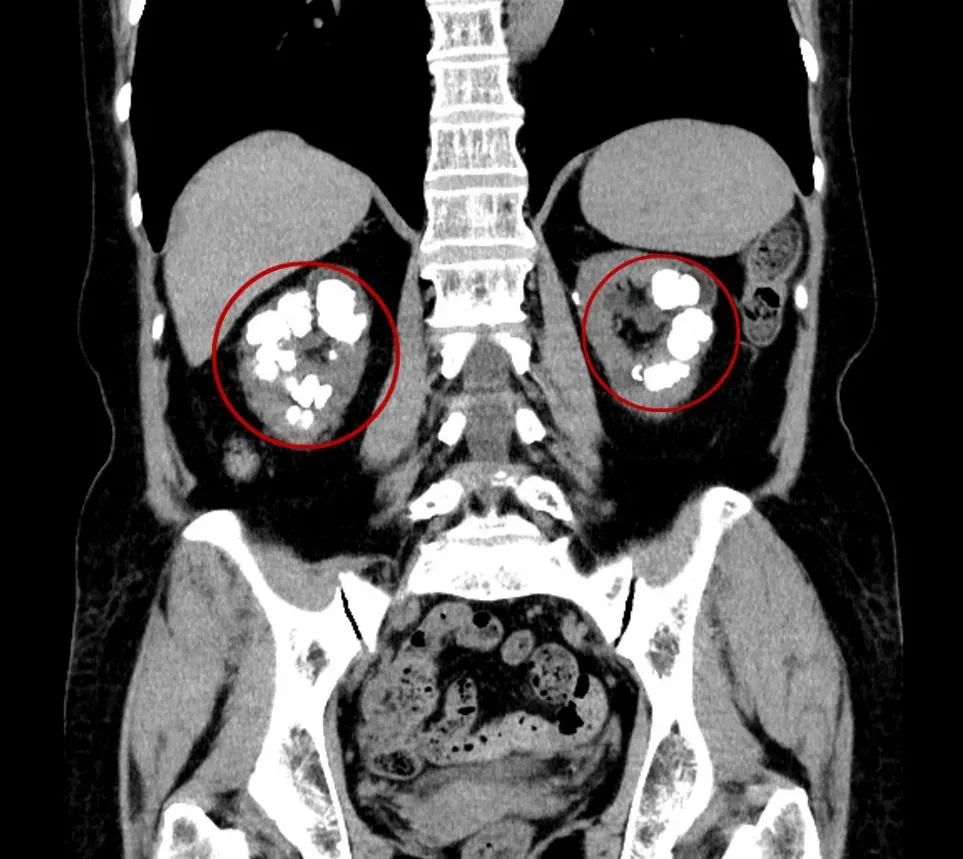

近两个月以来,甘阿姨自觉尿量变少了 ,到医院去看,竟发现两边的肾脏都长满了结石,还都是结石中最难处理的铸型结石。

更为棘手的是,甘阿姨两侧肾脏还出现了功能不全的现象,两侧肾的功能加起来只有正常人肾功能的1/4 ,为了避免肾脏功能继续恶化下去,必须马上做手术。

▲两侧肾脏及结石

铸型结石,也称鹿角型结石,是肾脏内的一种特殊形状的结石,因其状似鹿角而得名,也因为它像水泥浇铸一样填充于肾脏的集合系统内而称铸型结石。